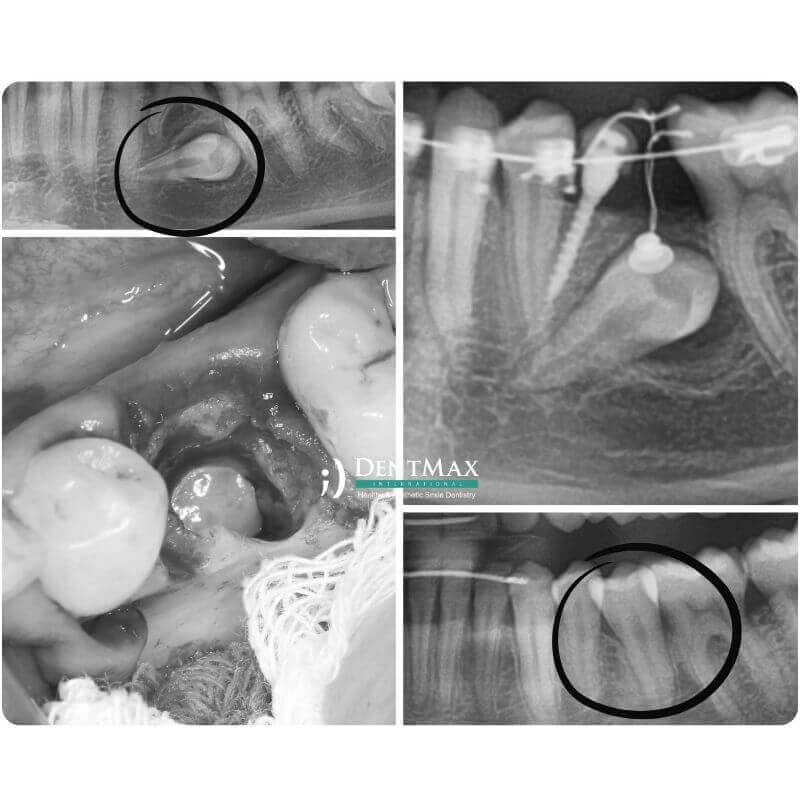

Impacted tooth exposure and traction is a combined orthodontic and surgical procedure used to guide unerupted permanent teeth (commonly canines) into their correct position in the dental arch. At DentMax Istanbul, we offer safe and effective impacted tooth guidance using digital planning and expert coordination between orthodontists and oral surgeons.

An impacted tooth is a permanent tooth that fails to erupt into the mouth at the expected time and remains embedded in the jawbone or soft tissue. It is most commonly seen with upper canine teeth but may involve other teeth.

CBCT or panoramic X-rays are taken to determine the exact position

A surgical procedure is performed to expose the impacted tooth

An orthodontic bracket or attachment is bonded to the tooth

Gradual traction is applied to guide the tooth into place